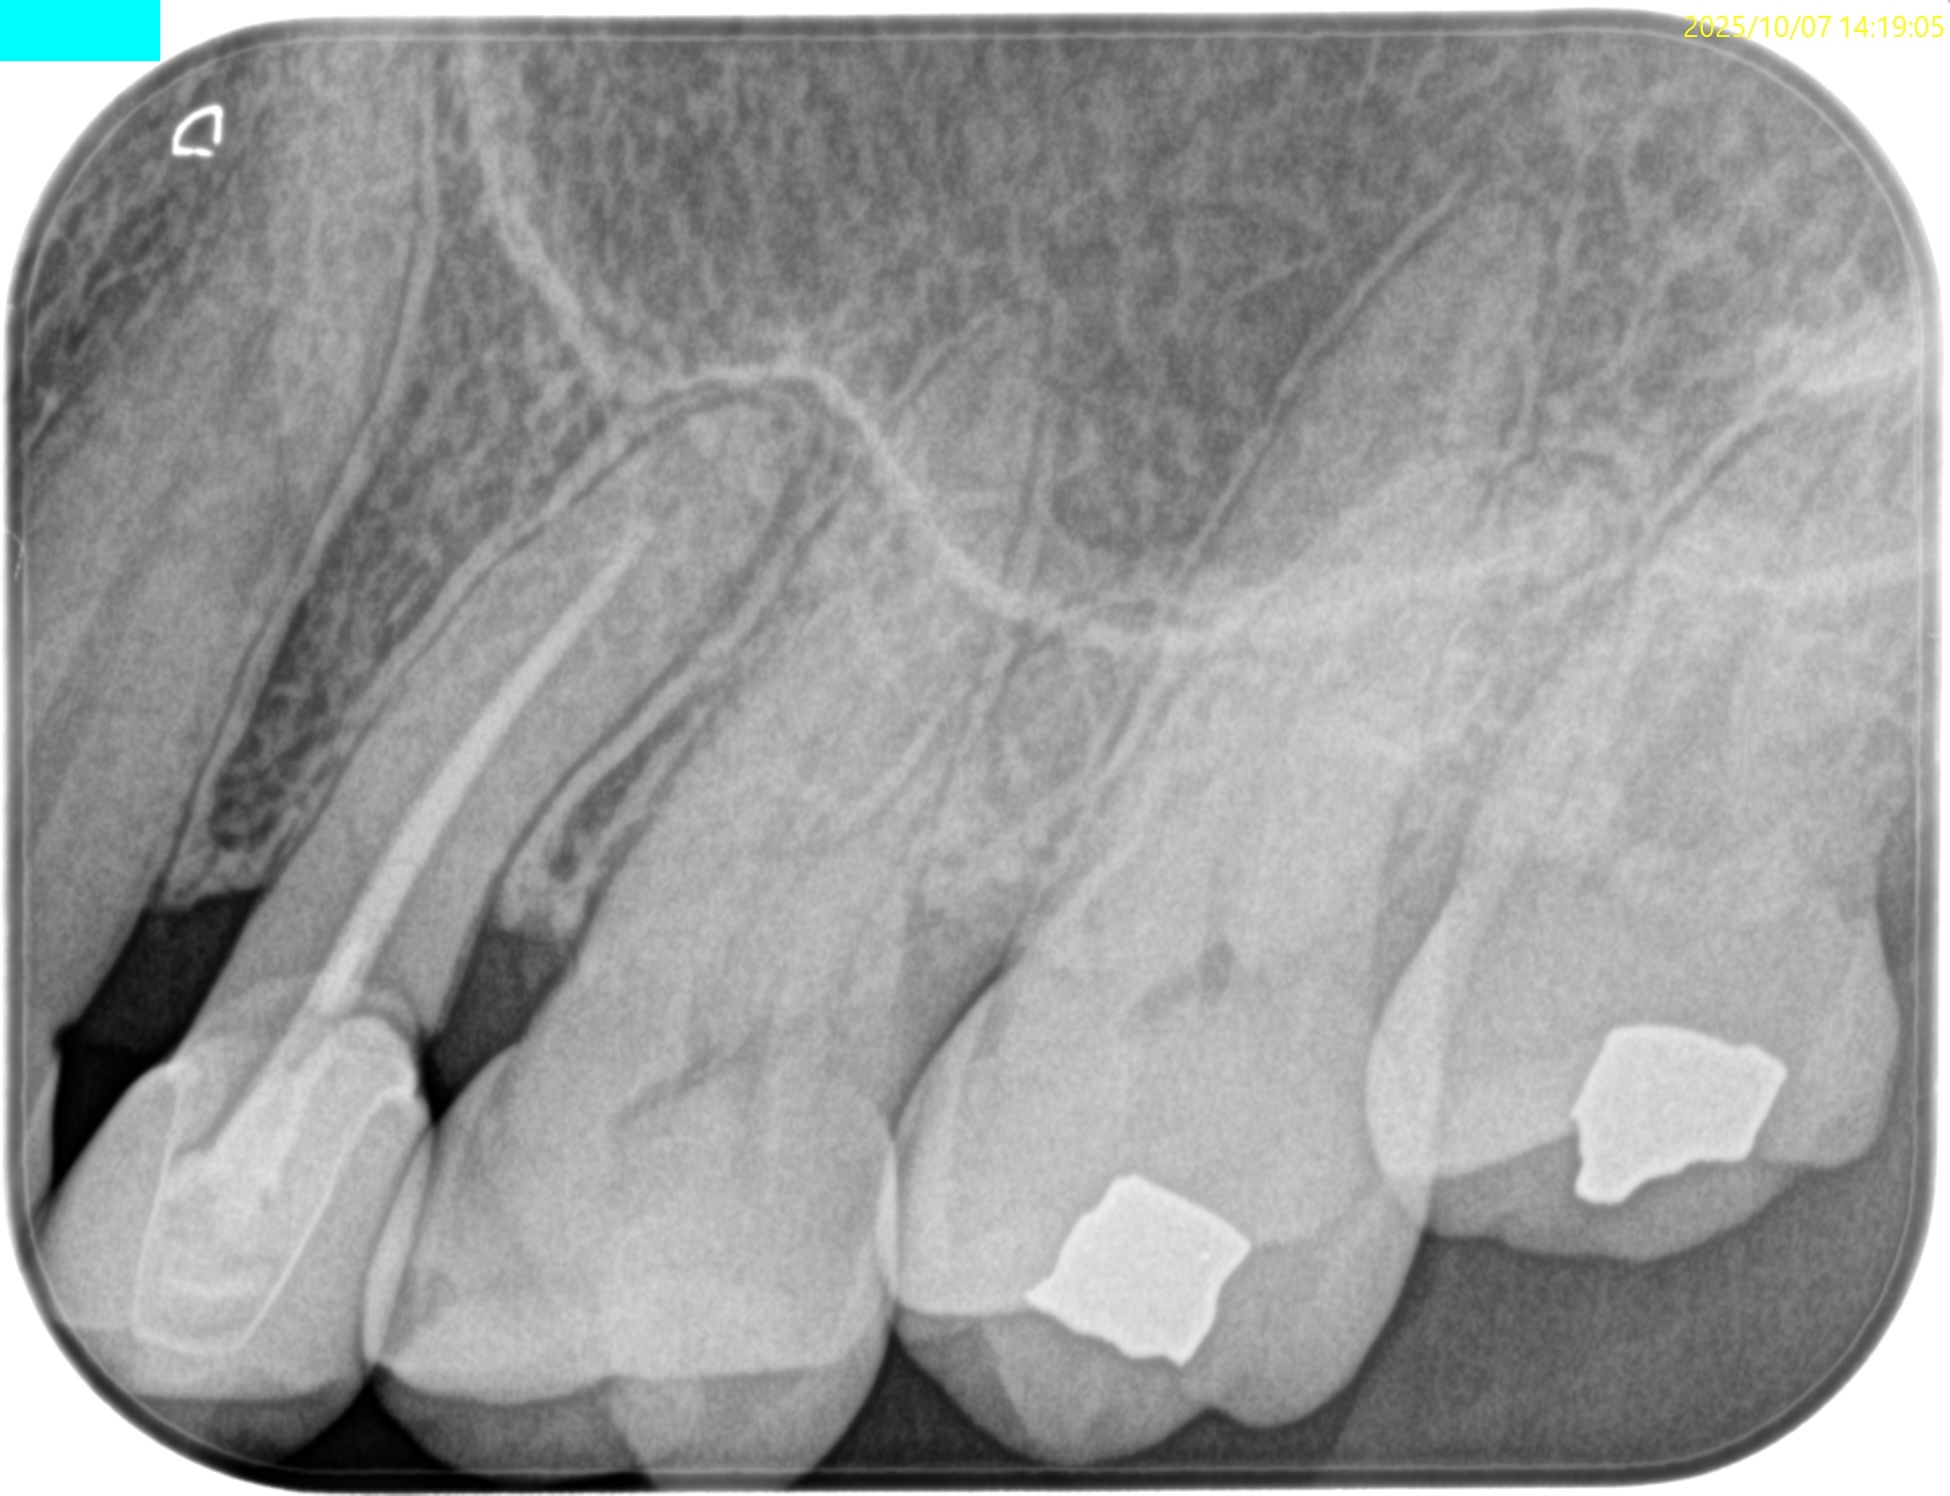

PA(2025.8.22)

もの詰まりはこの#13の遠心の築造体が剥き出しのマイクロリーケージであろう。

CBCT(2025.8.22)

#13 遠心のマージンが歯肉縁下でクラウンが不適合だ。ここにものが詰まるようだ。

これが患者さんの主訴である。

また、根尖病変があり根管形成・根管充填が太くなされていることからApicoectomyへ移行することになった。